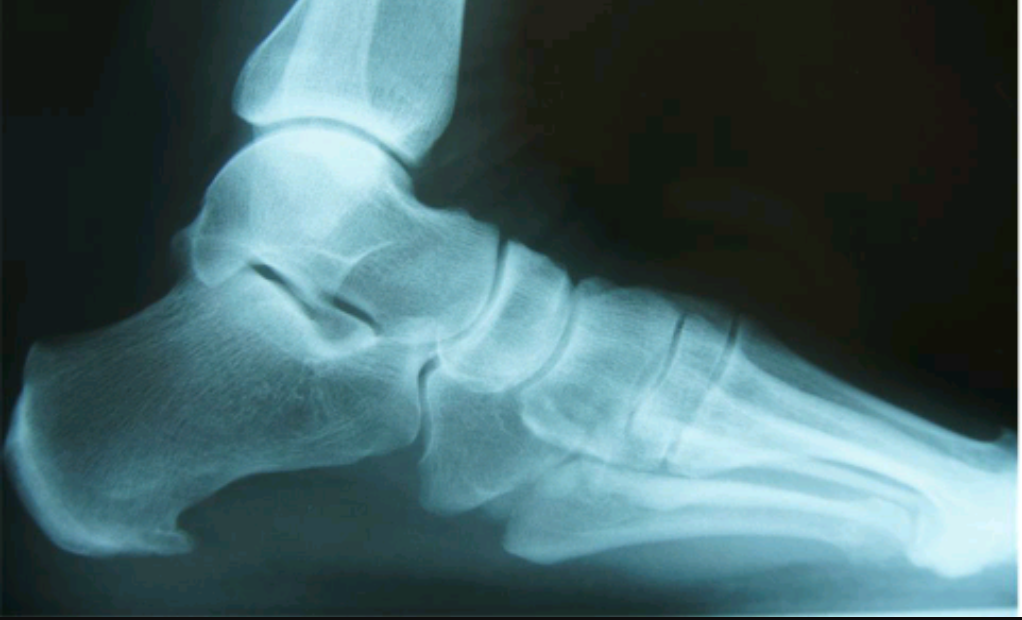

Name the feature. What kind of change is this? What disease is this associated with?

heel spur

inflammatory enthesopathic change

DJD